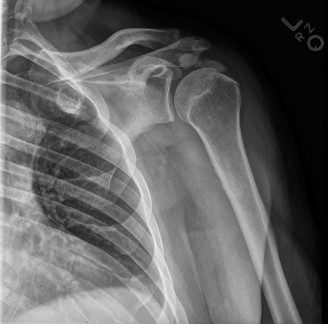

A 55-year-old, right-hand-dominant female presents with right shoulder pain for 6 months. She localizes the p…